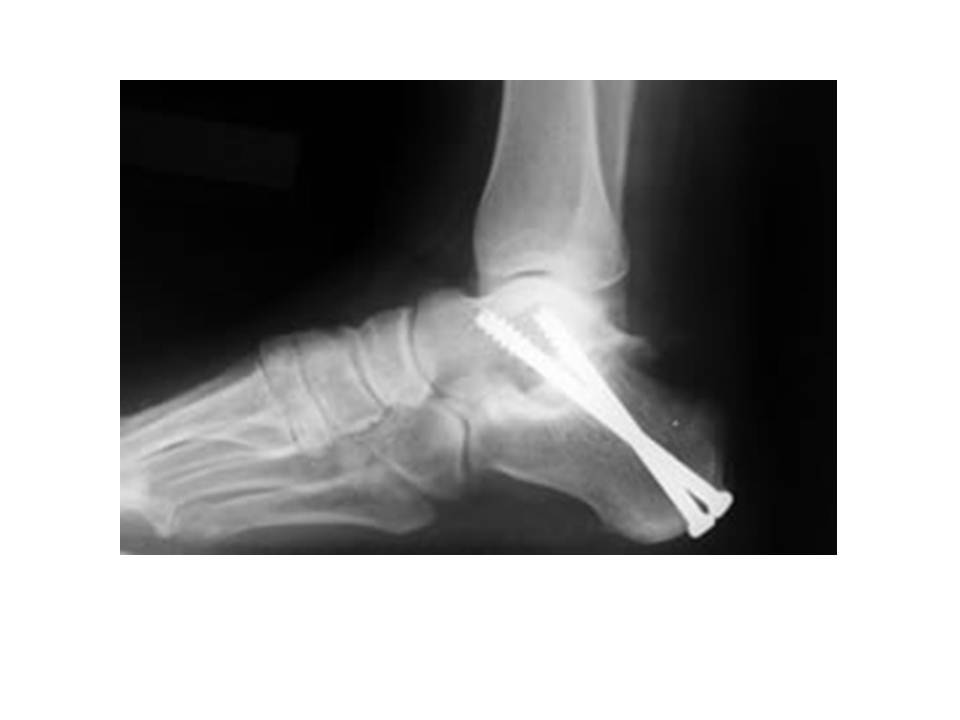

Ankle Arthrodesis Foot & Ankle Orthobullets Foot Arthritis Orthobullets It can make it difficult to walk and even stand without pain. arthritis can cause pain and stiffness in any joint in the body, and is common in the small joints of the foot and ankle. unlike osteoarthritis, which typically affects one specific joint, symptoms of rheumatoid arthritis (ra) usually appear in both feet, affecting the same joints.. Foot Arthritis Orthobullets.

Ankle Arthrodesis Foot & Ankle Orthobullets Foot Arthritis Orthobullets midfoot arthritis is defined as arthritis of the midfoot which includes the following joints: plantar fasciitis is a condition that causes pain on the bottom of the heel. arthritis can cause pain and stiffness in any joint in the body, and is common in the small joints of the foot and ankle. Aafd is a complex pathology. Foot Arthritis Orthobullets.

Ankle Arthrodesis Foot & Ankle Orthobullets Foot Arthritis Orthobullets Midfoot arthritis is a type of arthritis that affects your foot. arthritis can cause pain and stiffness in any joint in the body, and is common in the small joints of the foot and ankle. It can make it difficult to walk and even stand without pain. unlike osteoarthritis, which typically affects one specific joint, symptoms of rheumatoid. Foot Arthritis Orthobullets.

Ankle Arthrodesis Foot & Ankle Orthobullets Foot Arthritis Orthobullets There is no cure for arthritis, but there are a. Aafd is a complex pathology consisting both of. midfoot arthritis is defined as arthritis of the midfoot which includes the following joints: Midfoot arthritis is a type of arthritis that affects your foot. It can make it difficult to walk and even stand without pain. hallux rigidus is. Foot Arthritis Orthobullets.

Ankle Arthrodesis Foot & Ankle Orthobullets Foot Arthritis Orthobullets plantar fasciitis is a condition that causes pain on the bottom of the heel. midfoot arthritis is defined as arthritis of the midfoot which includes the following joints: unlike osteoarthritis, which typically affects one specific joint, symptoms of rheumatoid arthritis (ra) usually appear in both feet, affecting the same joints. ankle arthritis is a common degenerative. Foot Arthritis Orthobullets.